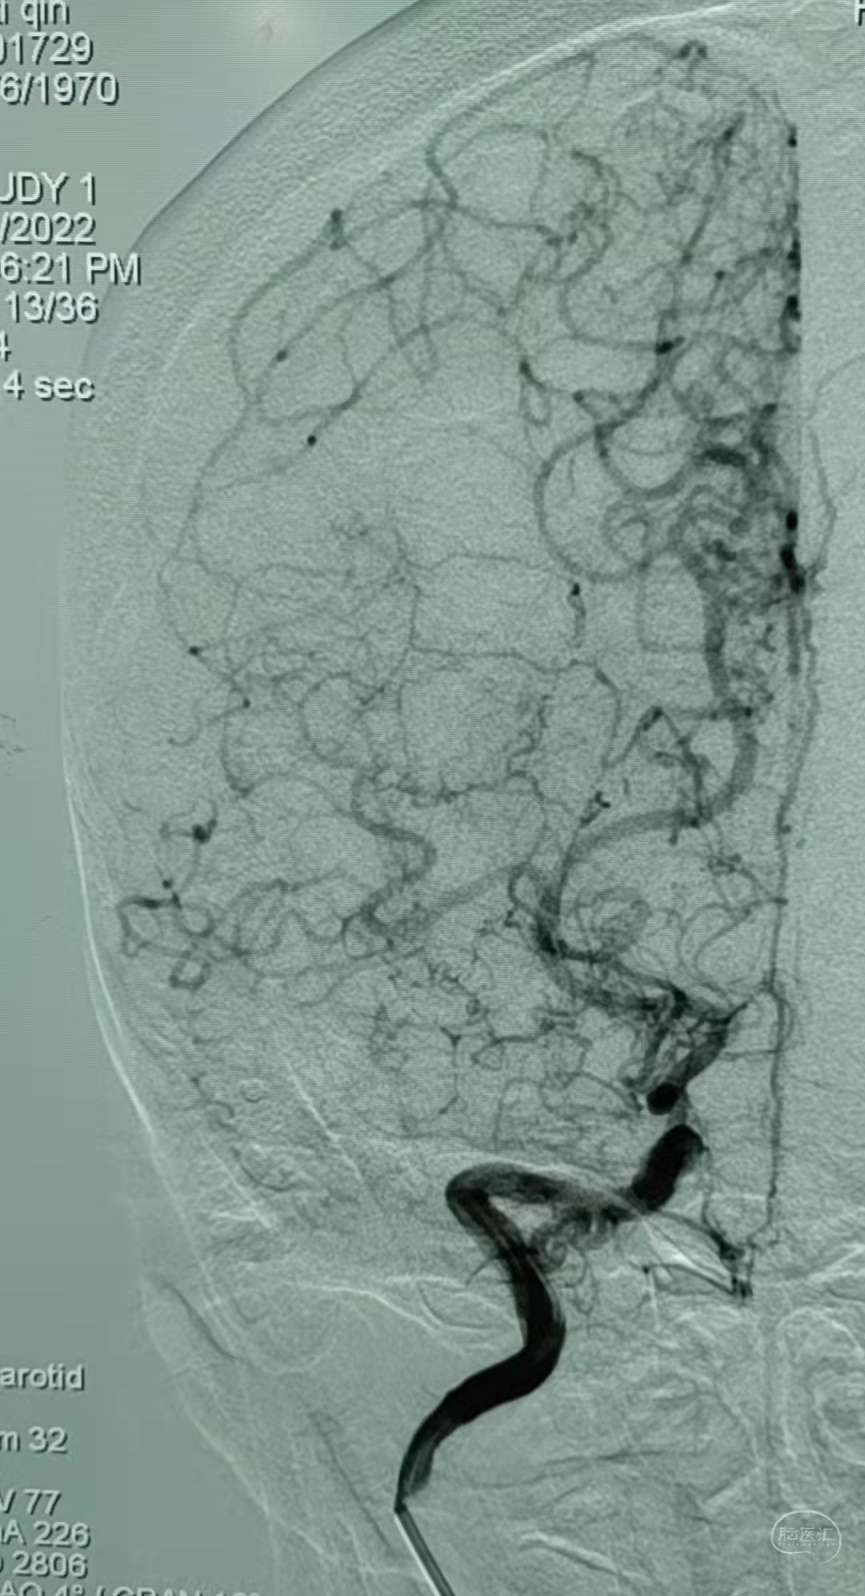

DSA:右侧大脑中动脉、大脑前动脉闭塞,烟雾样血管形成。

DSA:左侧大脑中动脉、大脑前动脉闭塞,烟雾样血管形成。

DSA:右侧大脑中动脉、大脑前动脉闭塞,烟雾样血管形成。

DSA:左侧大脑中动脉、大脑前动脉闭塞,烟雾样血管形成。